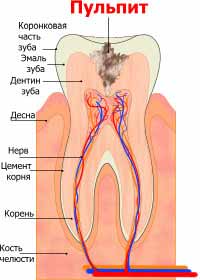

Пульпит

Пульпит

Среди осложнений кариеса пульпит занимает одно из лидирующих мест по частоте заболеваемости. Пульпит возникает при воспалении пульпы – сосудисто-нервного пучка зуба. Причинами патологии может стать не только кариес но и неправильные действия стоматолога или инфицирование пульпы через апикальное отверстие.

Пульпиты могут быть острыми и хроническими. Острая форма заболевания возникает при попадании инфекции в пульпу: серозное очаговое воспаление через время становиться гнойным, гной накапливается в пульпарной камере и развивается экссудат. Хроническая форма преимущественно является последствием острого пульпита.

Хронические пульпиты имеют несколько разновидностей: фиброзную, гипертрофическую и гангренозную формы. При фиброзном пульпите волокнистая соединительная ткань разрастается, при гипертрофическом – выходит в открытую кариозную полость, а при гангренозном пульпите ткань в пульпе распадается.

Причины пульпита

Причинами пульпита являются чаще всего микробы, продукты жизнедеятельности которых губительно влияют на пульпу. Инфекция попадает в пульпу по дентинным канальцам, но пульпит способен развиться и после травмы зуба, в особенности его перелома. Также заболевание может возникнуть из-за неправильной работы стоматолога и некачественной механической обработки. Интактная пульпа подвергается действию инфекции и воспаляется.

Среди других причин, которые способствуют развитию заболевания, выделяют действие некоторых химических веществ (ортофосфорной кислоты, пломбировочного материла, антисептиков) и хирургические манипуляции, такие как инъекции в десну, гингивотомия, гингивэктомия.

Симптомы пульпита

Симптомы пульпита зависят от его формы. Общими клиническими проявлениями принято считать сильную зубную боль которая длится непрерывно и приходит чаще всего ночью. Начинается заболевание с неприятных, ноющих ощущений, но с развитием болезни боль становится пульсирующей и сильной.

Острый пульпит делает больной зуб очень чувствительным к прикосновениям и постукиваниям, холоду и горячей пище. Течение хронического пульпита преимущественно бессимптомное, а боль приходит только во время обострений. Симптомом гипертрофического пульпита является появление фиброзного полипа в кариозной полости. Обнаженная пульпа более подвержена инфекциям и постоянно страдает от механического раздражения. Для хронического гангренозного пульпита характерна сильная боль, особенно при прикосновении горячей еды и питья. При этом холод способен значительно снизить болевые ощущения.

Неправильное или несвоевременное лечение пульпита может привести к серьезным последствиям – периодонтиту (воспалению периодонта, проходящему с повреждением целостности удерживающих зуб связок, костной ткани и образованием больших кист).

Лечение пульпита

Существует ряд методов лечения пульпита. Консервативный метод аналогичен лечению кариеса и подходит для молодых людей. При нем доктор сохраняет жизнеспособность пульпы. Пораженная полость обрабатывается медикаментозно, применяют антисептики, антибиотики и протеолитические ферменты (применяется редко из-за большого риска осложнений). Лечат заболевание и хирургическим путем, удаляя воспаленную пульпу и пломбируя канал зубного корня. Удаление пульпы проводят с местным наркозом, либо после умерщвления нерва.

Избежать пульпита можно, выполняя профилактические меры. Прежде всего человек должен правильно ухаживать за ротовой полостью и своевременно лечить кариес, не откладывая в долгий ящик поход к стоматологу. Необходимо помнить, что пульпит чреват развитием серьезнейших осложнений (периодонтит, некроз пульпы), лечение которых будет более болезненным и дорогим.